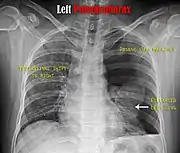

Computed tomography

CT with the identification of underlying lung lesion: an apical bulla on the right side

A CT scan is not necessary for the diagnosis of pneumothorax, but it can be useful in particular situations. In some lung diseases, especially emphysema, it is possible for abnormal lung areas such as bullae (large air-filled sacs) to have the same appearance as a pneumothorax on chest X-ray, and it may not be safe to apply any treatment before the distinction is made and before the exact location and size of the pneumothorax is determined.[15] In trauma, where it may not be possible to perform an upright film, chest radiography may miss up to a third of pneumothoraces, while CT remains very sensitive.[18]

A further use of CT is in the identification of underlying lung lesions. In presumed primary pneumothorax, it may help to identify blebs or cystic lesions (in anticipation of treatment, see below), and in secondary pneumothorax, it can help to identify most of the causes listed above.[15][19]